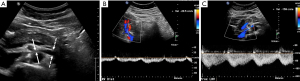

The screening examination of choice is DUS, offering both anatomic and physiologic assessment of the LRV absent radiation. However, the technique can be challenging, requires 6–8 hours fasting, and definitions vary depending on position (supine versus upright) (33). Reference ratios are slightly higher in the upright position, thought to be related to gravity acting on bowel and mesentery, pulling the SMA downward and pronouncing the LRV stenosis. Peak systolic velocity (PSV) is evaluated in the compressed, AM LRV and compared to hilar PSV. Various ratios have been proposed as significant, ranging from 4.0:1 to 5.0:1 (Figure 4) (34-36).